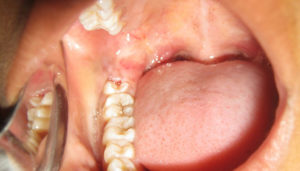

Перикоронит на фотографии

При наличии симптомов воспаления десны необходимо посетить стоматологическую клинику и проконсультироваться со специалистом для определения тактики лечения и предотвращения развития осложнений.